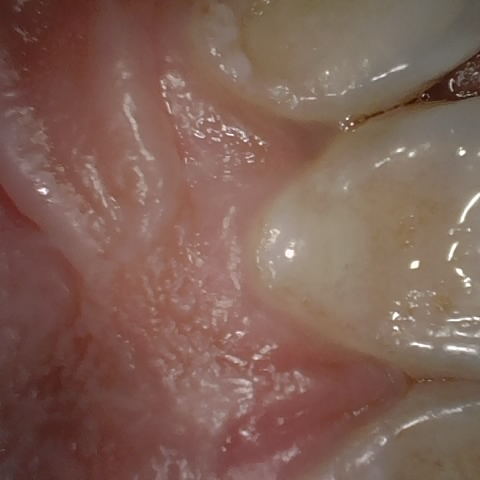

Annotated as "Good"